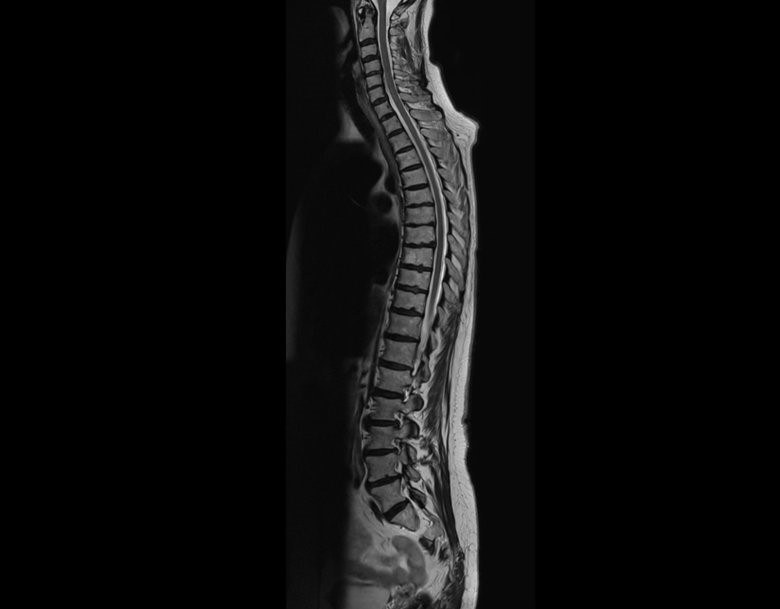

Magnetom Flow 是西門子醫療的第一個 1.5T 平台,具有封閉的氦氣迴路,不需要淬火管;而只需 1 分 22 秒即可取得整個脊椎的高解析度矢狀 T2 影像。(source:Siemens Healthineers)